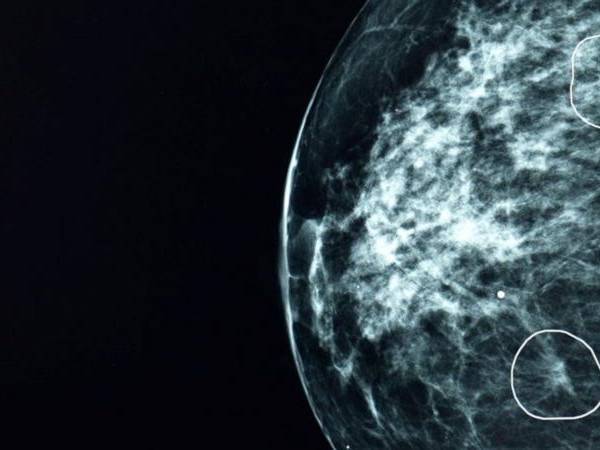

Tumor de cáncer

FUENTE DE LA IMAGEN,GETTY IMAGES

Pie de foto,

Pacientes de cáncer con tumores inferiores a los 15mm tienen una tasa del 90% de supervivencia durante los siguientes cinco años.